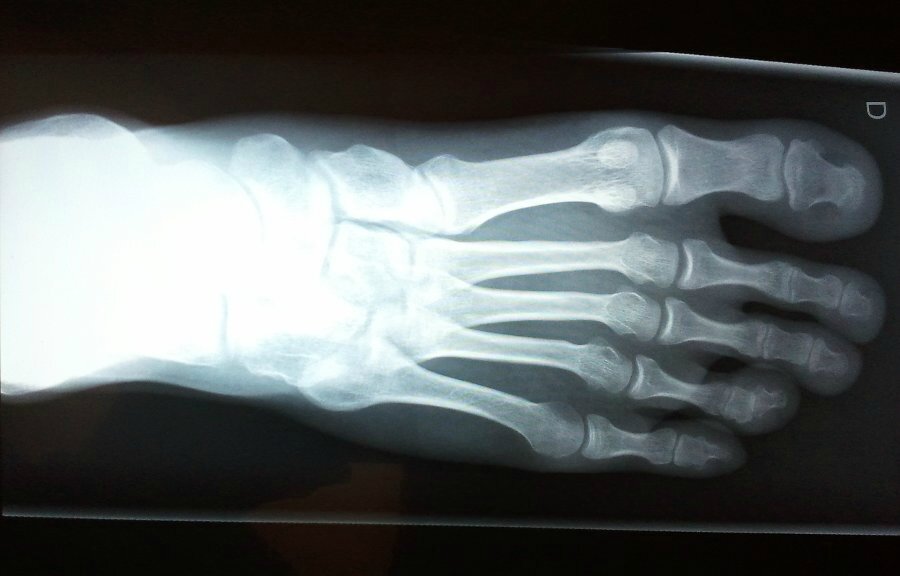

janvier 15, 2023. Le névrome de Morton est une maladie qui touche les nerfs du pied, entre le troisième et le quatrième orteil. Aussi appelée « neurome plantaire » ou « neurome de l'avant-pied », cette pathologie entraîne une douleur intense et persistante. Ensemble, découvrons l'essentiel sur le névrome de Morton dans ce guide.. Bien qu'il ne présente aucun symptôme externe, le névrome de Morton provoque plusieurs sensations désagréables sur différentes régions du pied. Engourdissement et picotement des orteils. Sensation de brûlure à l'avant du pied. Sensation d'avoir un bas roulé ou avec un pli derrière les orteils. Sensation de petites décharges.

Le syndrome de Morton se caractérise par une douleur de l'avant-pied: la plante du pied brûle ou chauffe.Les femmes de plus de 50 ans sont particulièrement touchées.. Quelle est la définition du syndrome de Morton ? Aussi appelé "le névrome de Morton", ce syndrome est une maladie qui touche le pied.Le syndrome se caractérise par une compression d'un nerf sensitif de l'avant-pied, au.. Névrome de Morton Généralités. Le névrome de Morton peut être à l'origine de douleurs de l'avant-pied. Les patients ressentent une douleur sourde en regard de la tête des métatarsiens située de part du névrome. Les douleurs peuvent irradient dans les orteils correspondants. Des paresthésies peuvent survenir dans ces mêmes régions.